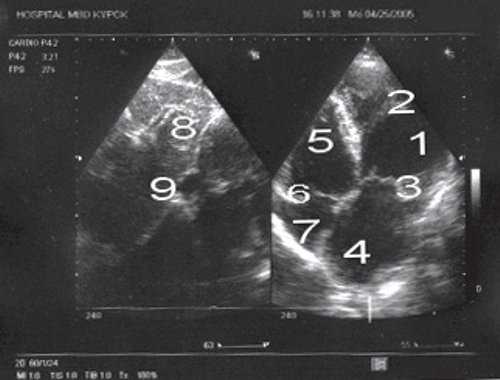

При проведении эхокардиографии в месте обычного расположения левого желудочка лоцировался анатомически правый желудочек, который верифицировался по наличию модераторного пучка. Анатомически правый желудочек соединялся с левым предсердием через трикуспидальный клапан, который лоцировался ближе к верхушке сердца по сравнению с митральным клапаном. Последний соединял морфологически левый желудочек с правым предсердием, в который впадала нижняя полая вена (рис. 1). Определялся параллельный ход магистральных артерий, при этом аорта лоцировалась слева и спереди от легочной артерии. Таким образом, имело место предсердно-желудочковое и желудочково-артериальное несоответствие. У пациента выявлялась также недостаточность митрального и трикуспидального клапанов. На последнем клапане отмечалось увеличение градиента давления (рис. 2, 3).

![Эхокардиограмма больного П (четырехкамерная проекция)]()

Рис. 1. Эхокардиограмма больного П. (четырехкамерная проекция).

1 - анатомически правый желудочек; 2 - модераторный пучок; 3 - трикуспидальный клапан; 4 - левое предсердие; 5 - анатомически левый желудочек; 6 - митральный клапан; 7 - правое предсердие; 8 - печень; 9 - нижняя полая вена.

![Трансмитральный поток у больного П ((импульсноволновая допплерография)]()

Рис. 2. Трансмитральный поток у больного П. (импульсноволновая допплерография).

![Транстрикуспидальный поток у больного П (постоянноволновая допплерография)]()

Рис. 3. Транстрикуспидальный поток у больного П. (постоянноволновая допплерография).

Имеющаяся допплер-эхокардиографическая картина была расценена как корригированная транспозиция магистральных сосудов, сочетающаяся с аномалией атриовентрикулярных клапанов. Пациент был направлен к кардиологу для дообследования и лечения.